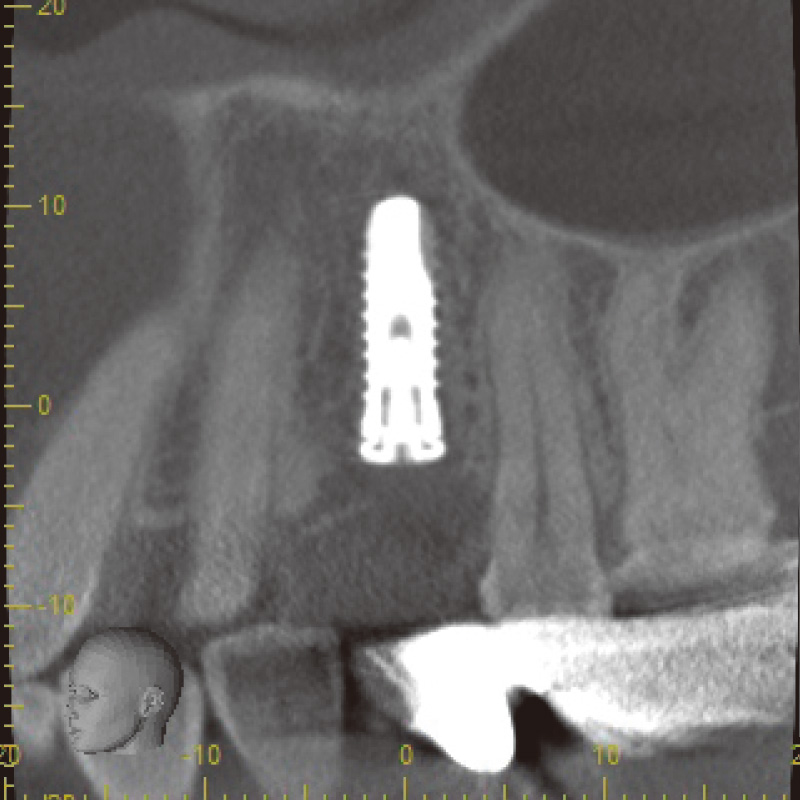

患者は73歳女性。主訴は「左上奥歯が食べ物をかむと痛む」とのこと。診査の結果、上顎左側第一小臼歯 (24)に慢性的な歯周炎と、根尖部透過像や歯根膜腔の拡大、歯根破折が認められた。40年以上前に治療を受けた既往歴があり、炎症の状況により患者抜歯後の即時インプラント埋入をその場で判断し行うこととなった(図1)。

図1 術前パノラマX-P(Veraview X800にて撮影) -